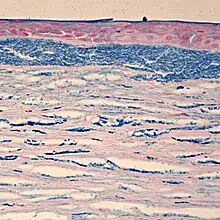

Colloidal iron staining shows deposition of glycosaminoglycans in the cornea

Macular Corneal Dystrophy is an autosomal recessive genetic disorder caused by mutations in the carbohydrate sulfotransferase gene (CHST6), resulting in abnormal proteoglycan synthesis. The accumulation of abnormal glycosaminogycans in the corneal epithelium and stroma leads to progressive opacification of the cornea and subsequent loss of visual acuity.[7][8] There are three variants of MCD characterized by immunophenotype:

Histopathological staining shows characteristic alcian blue-positive deposits.[7] Various imaging modalities, including confocal microscopy and ocular coherence tomography, can provide information about the changes within the cornea and may be suitable replacements for tissue biopsy and excision.[8]